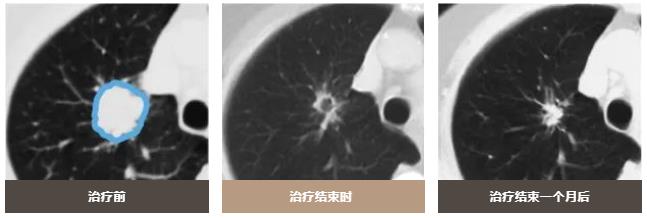

质子治疗可以减少对周围正常肺组织的照射剂量,只对病变部位进行集中照射。

6.6 GyE×10次,总剂量66GyE与以往80 GyE/20 次是生物等效剂量,预计可获得同样的治疗效果。目前正在进行安全性和有效性的临床试验。